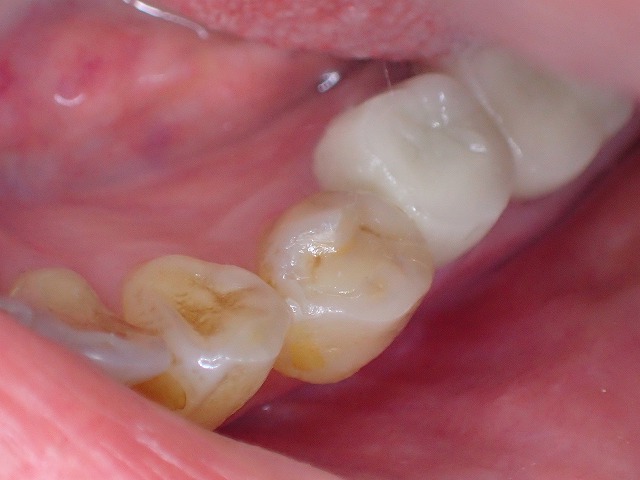

ジルコニアのインレーは適合悪いでおすすめできません。

ジルコニアではんく インレーはe.maxセラミックがおすすめ